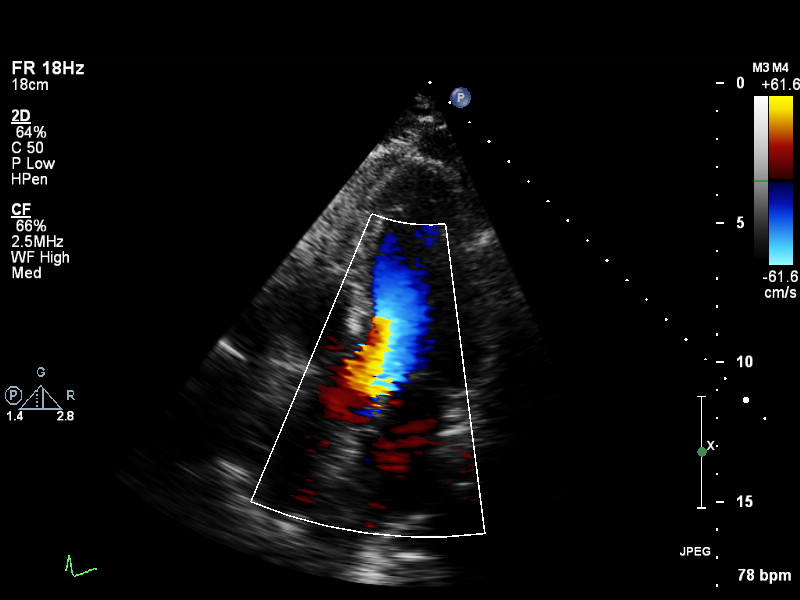

ImageView NameDescription

a3ch-outflow a3ch-outflow A3CH emphasizing LVOT (colour focused on LVOT or limited b&w of LVOT area)

a4ch-full a4ch-full Apical 4-chamber showing the full depth of all four chambers (no LV/RV focus)

a4ch-ias a4ch-ias Apical 4-chamber, focused on the inter-atrial septum

a4ch-la a4ch-la A4CH with Doppler near MV/LA or 2D covering full LA, not full LV

a4ch-lv a4ch-lv A4CH covering the whole depth of the LV, not the whole depth of the LA

a4ch-ra a4ch-ra Apical 4-chamber focused on the right atrium, or colour Doppler on TV/RA

a4ch-rv a4ch-rv Apical 4-chamber focused on the right ventricle

a5ch-full a5ch-full Apical 5-chamber from apex to back of the atria, no LVOT colour

a5ch-outflow a5ch-outflow A5CH including LVOT; may lack full depth or has LVOT colour

apex apex Any apical window whose depth is insufficient to reach the mitral ring